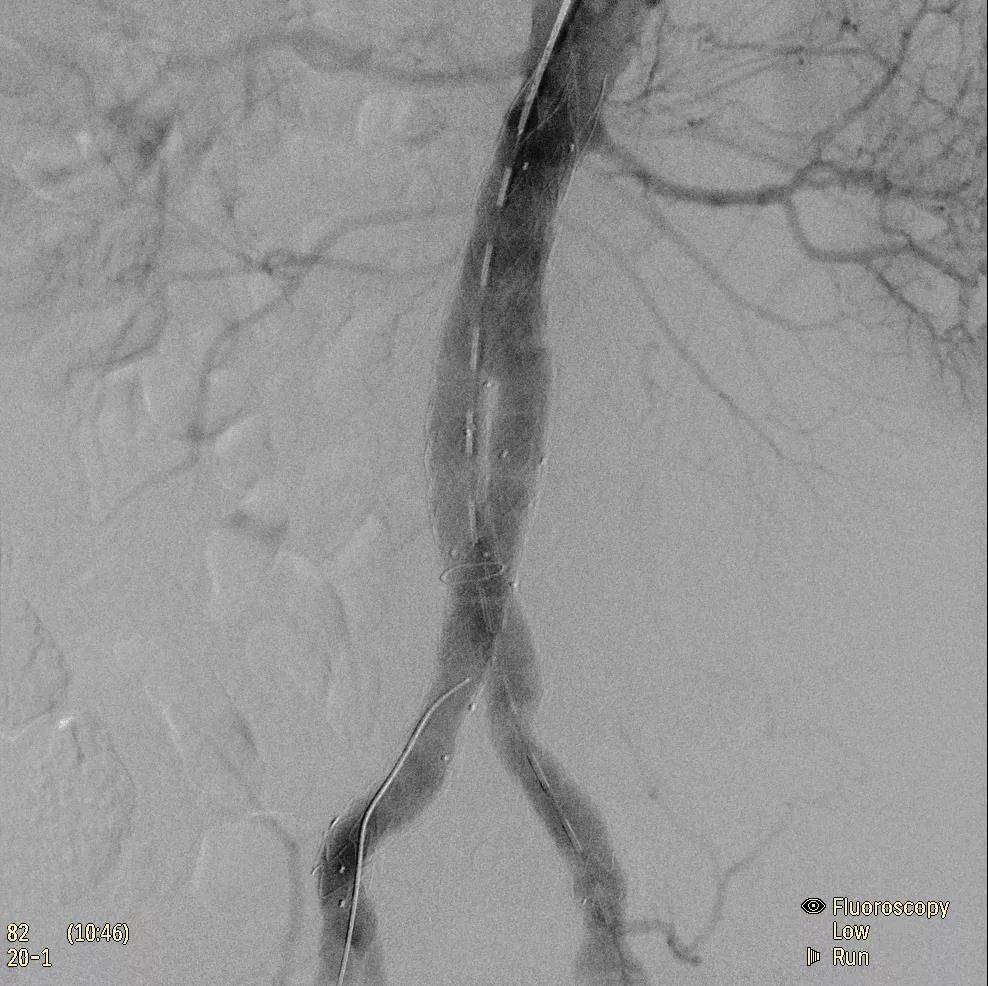

為了獲得清晰的高質(zhì)量圖像,Zenition 70 采用了與公司Azurion平臺相同的圖像處理算法,可提供患者解剖結(jié)構(gòu)的高清可視化和更大的可視區(qū)域。飛利浦的MetalSmart軟件等功能可確保圖像質(zhì)量,該軟件可自動調(diào)整圖像的對比度和亮度,以便在視野中存在金屬物體(如植入物)時提高圖像質(zhì)量 - 這一特性使Zenition 70在整形外科中特別有用。